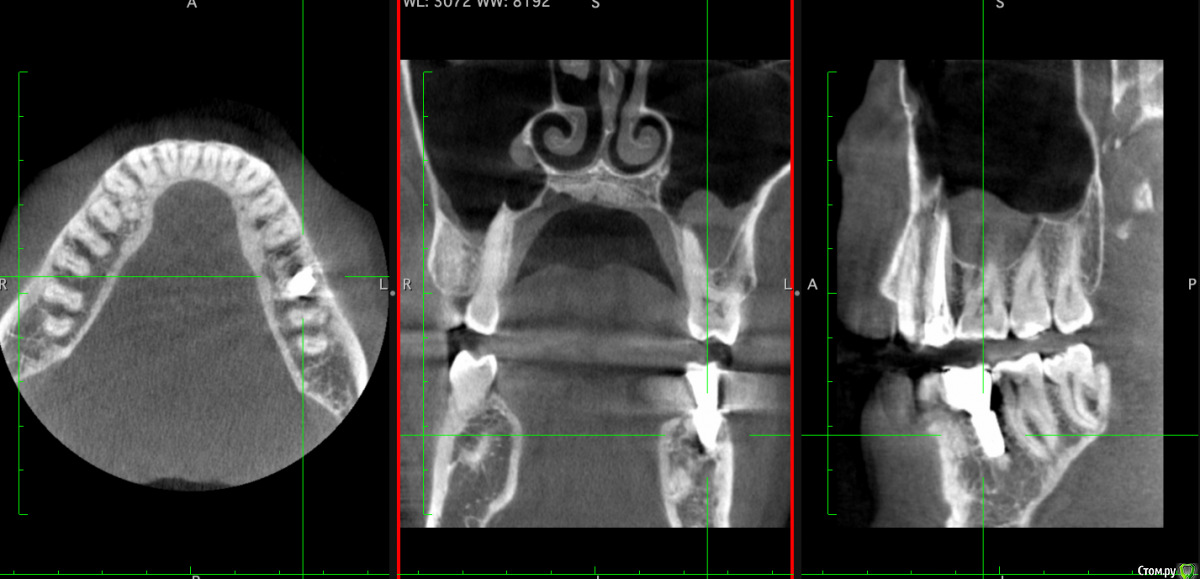

Nikitas Опубликовано 26 марта, 2019 Поделиться Опубликовано 26 марта, 2019 Восемь месяцев назад удален 36 зуб (на верхушках обоих корней был периодонтит), и одномоментно установлен имплантат. Полости, в которых было воспаление были заполнены графтом. На снимках КТ вокруг имплантата видны "полости", похоже что костной ткани в них нет. Уважаемые доктора, оцените пожалуйста, насколько такая степень приживления имплантата спустя 8 месяцев удачна, и каков прогноз? Будут ли эти полости зарастать костной тканью и насколько большая вероятность, что в них попадет инфекция? Насколько существенно, что имплантат установлен немного под наклоном? Субъективно жалоб нет. Ссылка на комментарий

Neilrus Опубликовано 26 марта, 2019 Поделиться Опубликовано 26 марта, 2019 чернота которую вы принимаете за пустоту - это шум от металла.Если вас ничего не беспокоит, то живите спокойно )наклон не беда. Ссылка на комментарий